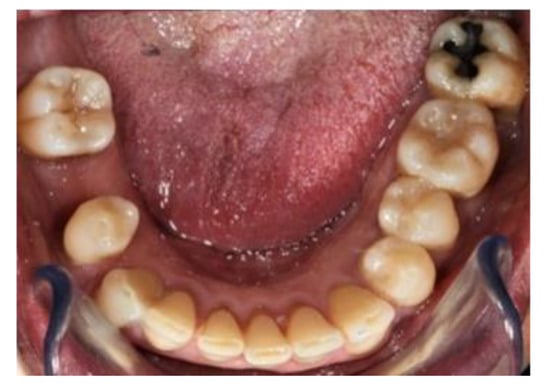

2. Case Report

The subject involved in this clinical study was a healthy woman, 54 years old. The request of this patient was to improve her mouth both functionally and aesthetically, which was altered because of the partial edentulism (Kennedy Class II). She asked to avoid any invasive surgery. During the anamnesis, she declared not to be affected by any systemic pathology (e.g., diabetes, hypercholesterolemia or hypertension). She also declared not to be affected by an allergy to any medication or similar drugs; she declared not to be subjected to any pharmacologic treatment except some analgesic therapy to treat sporadic headaches. The patient claimed to smoke 20 cigarettes a day for more than 20 years. The next step was to perform an objective examination, associated with a series of intraoral pictures (Figure 1, Figure 2, Figure 3, Figure 4 and Figure 5) and to the analysis of a radiographic exam (orthopantomography, Figure 6) that was acquired 10 months earlier when the same subject underwent the therapy and the teeth extraction 4.7–4.8. The objective examination showed poor oral hygiene, with plaque accumulation as well as the presence of many pigmentations due to excessive smoking. The radiography showed bilateral bone atrophy together with periodontal damage for most of the residual dental elements. These conditions represented a limitation to the insertion of implants for a fixed prosthesis.

Figure 5. Lower view.

Prosthesis 03 00038 g005